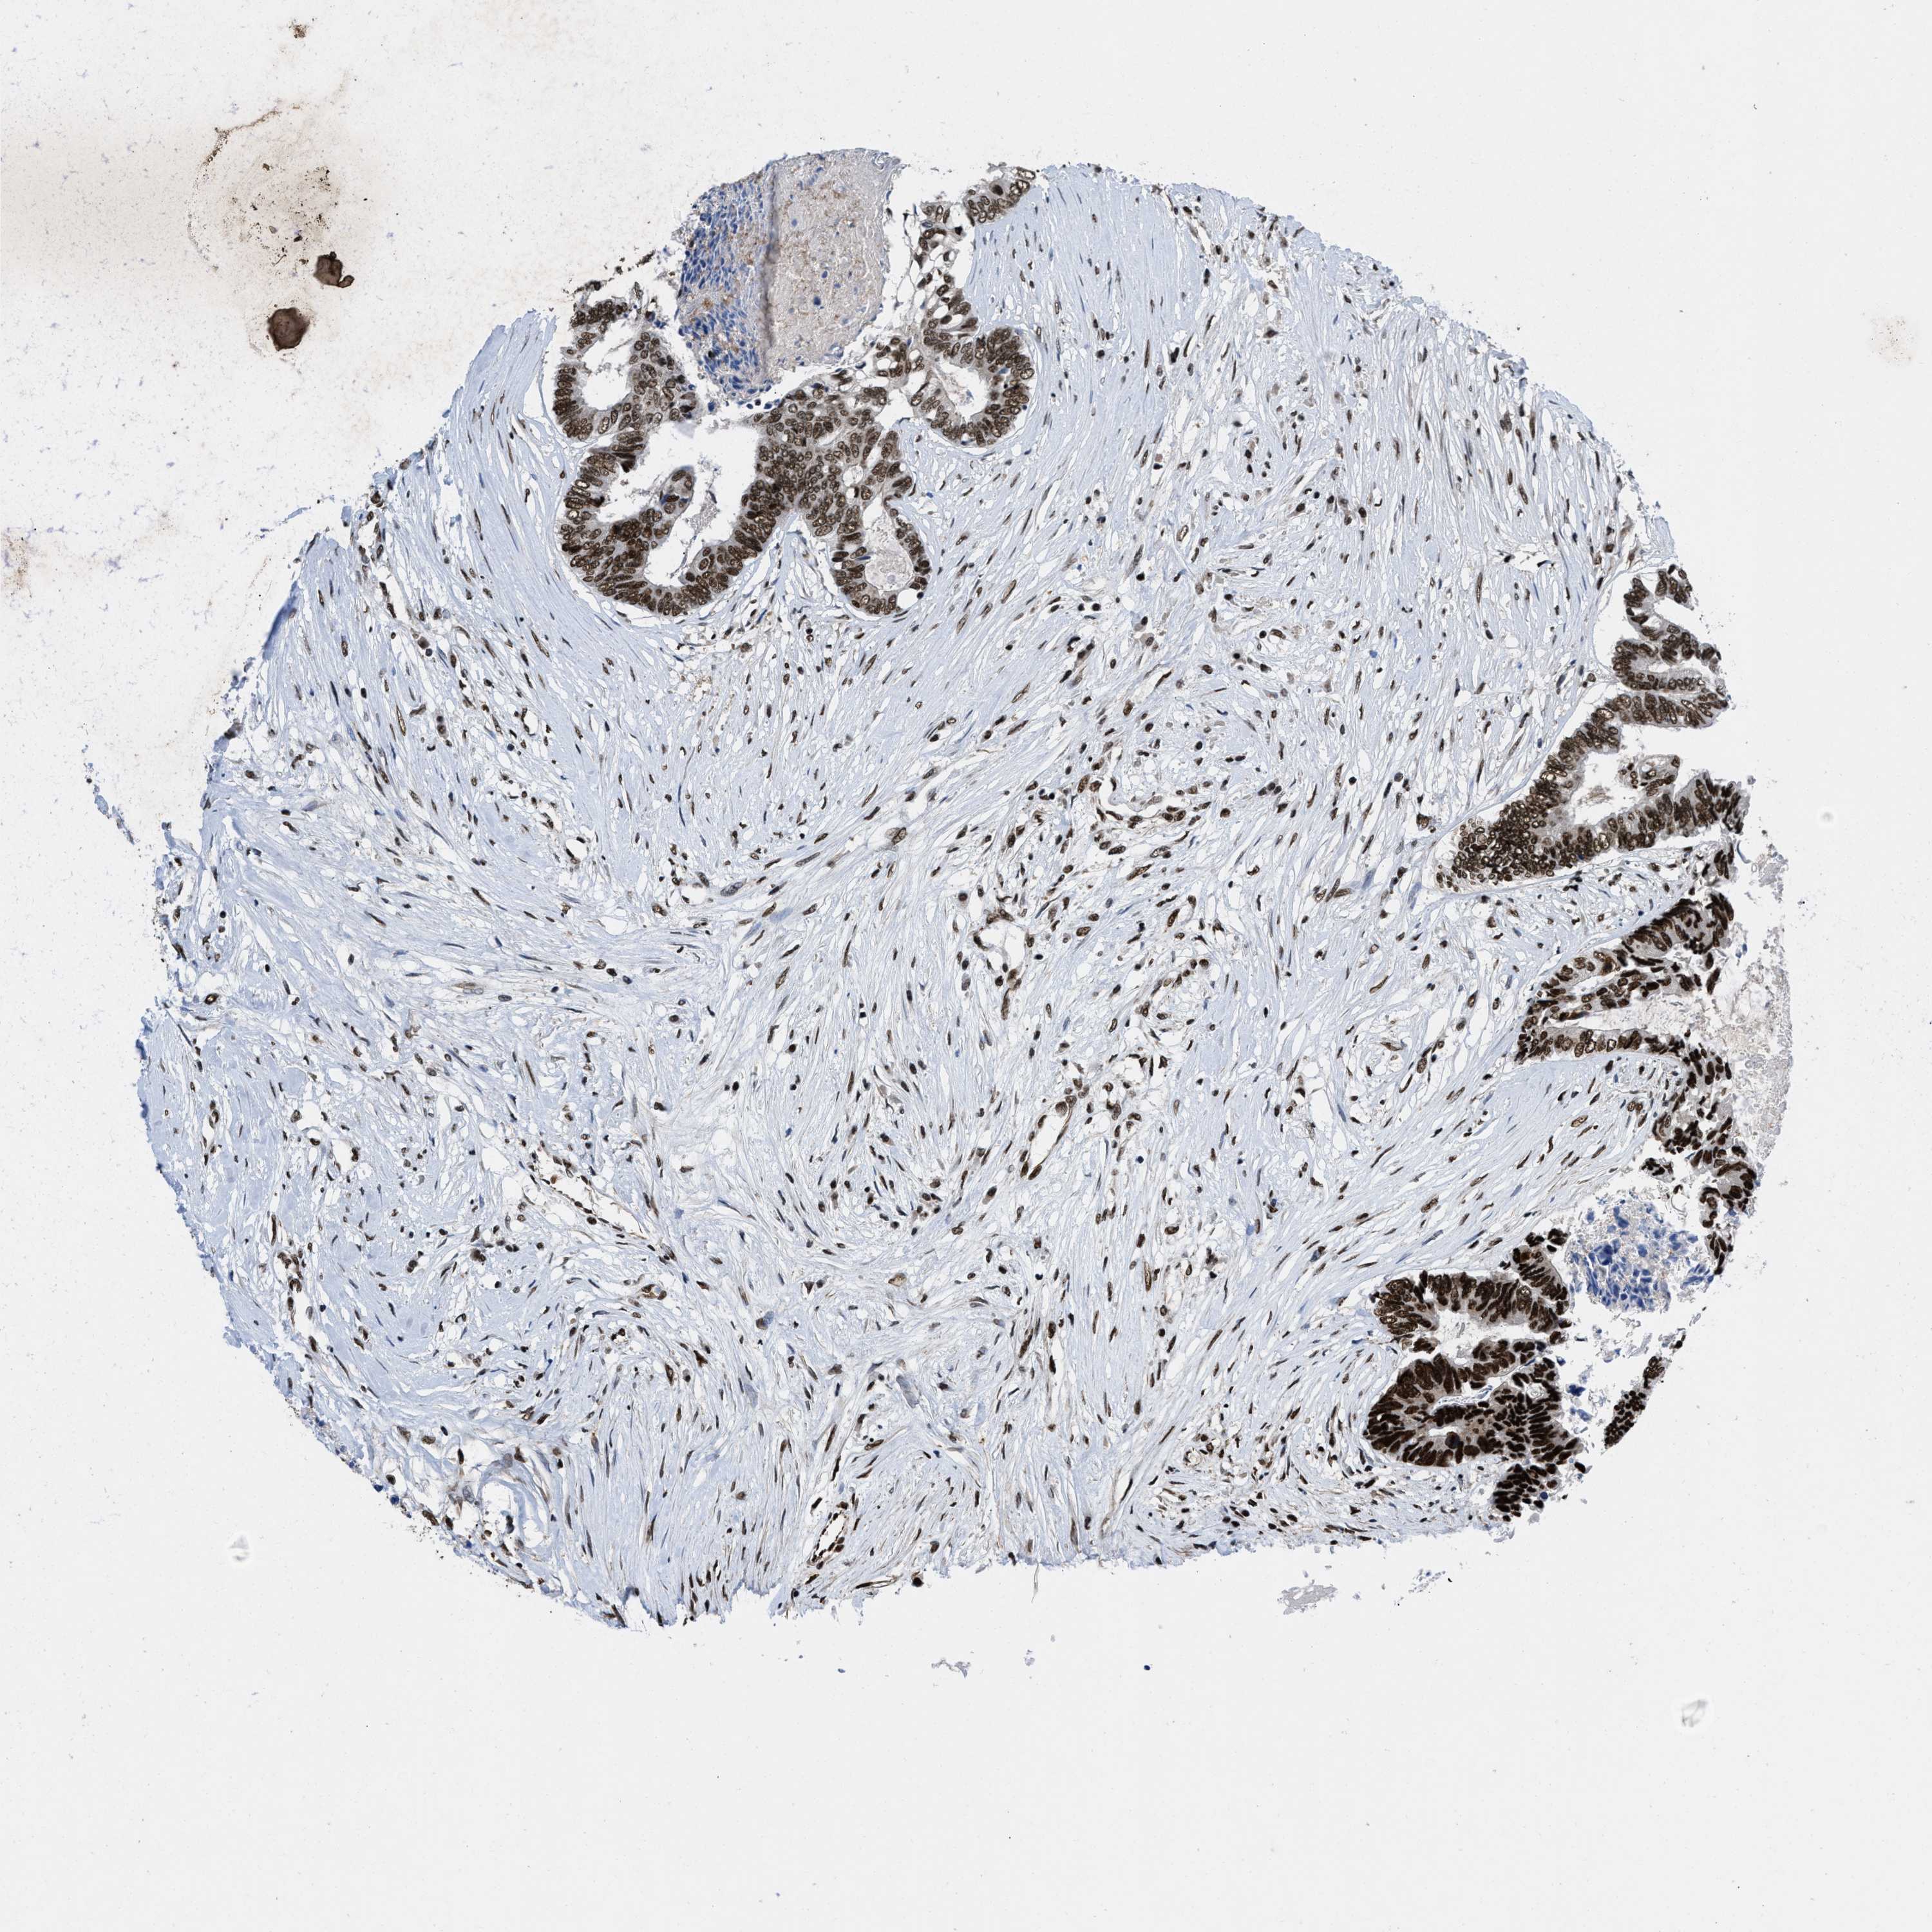

CANCER COLORECTAL CANCER Show tissue menu

Colorectal cancer

Human cancer

Colon adenocarcinoma